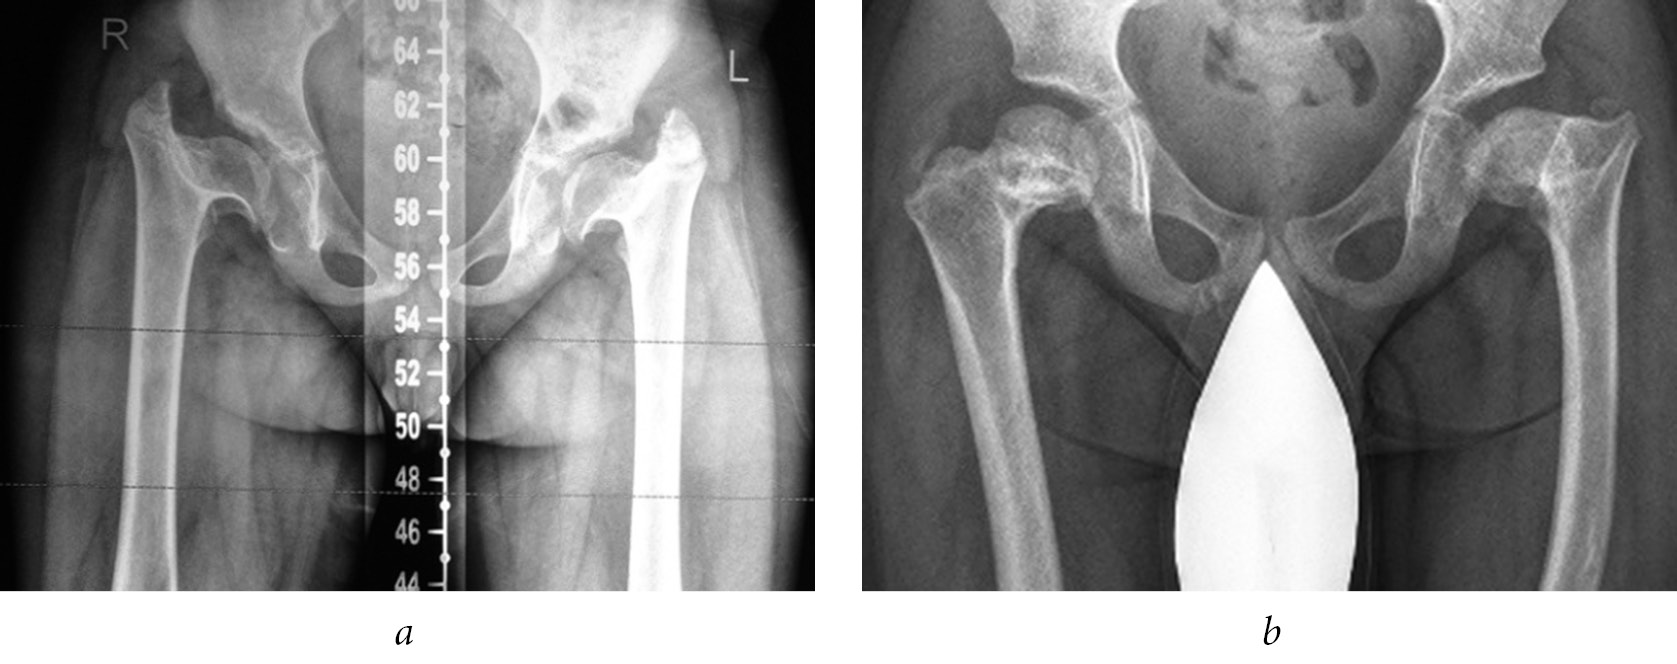

In our series of cases, in 8 out of 12 (66.7%) patients, we noted lesion to the proximal growth zones of the femoral bone with the formation of varus deformities of the necks, which necessitated surgical correction (Fig. 4).

Fig. 4. Radiographs of the hip joints of patients K. (a) and A. (b) with varus deformities of the femoral necks